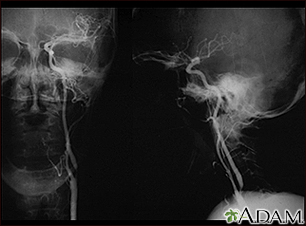

Carotid stenosis - X-ray of the left artery

• Angiogram of the head to look for a blood vessel that is blocked or bleeding

• Carotid duplex (ultrasound) to see if the carotid arteries in your neck have narrowed

• Magnetic resonance angiography (MRA) or CT angiography to check for abnormal blood vessels in the brain